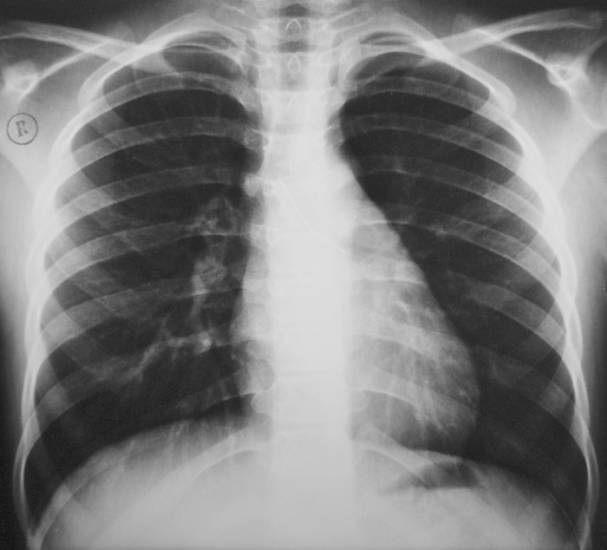

Поставить диагноз при паховой грыжи с левой или правой стороны, а также при пупочном выпячивании можно на осмотре у абдоминального хирурга без инструментального исследования. В случае внутренней грыжи без внешнего дефекта потребуется рентгенологическая и гистологическая диагностика.

Рентгенография грудной полости с применением контрастного вещества помогает поставить точный диагноз, определить расположение диафрагмальной грыжи (слева или справа), увидеть степень поражения.